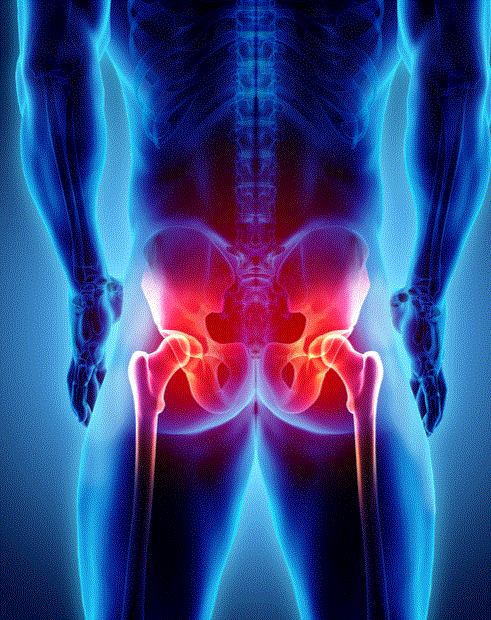

어깨 석회성건염만 아니라 고관절 통증 유발하는 석회도 있다?

우리몸의 관절은 여러 가지 종류가 있습니다. 어깨, 무릎, 척추, 고관절 등 임상에서 주로 다뤄지는 관절은...